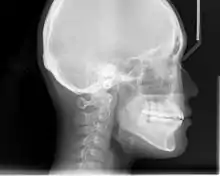

Lateral cephalometric radiographs

Lateral cephalometric radiograph is a radiograph of the head taken with the x-ray beam perpendicular to the patient's sagittal plane. Natural head position is a standardized orientation of the head that is reproducible for each individual and is used as a means of standardization during analysis of dentofacial morphology both for photos and radiographs. The concept of natural head position was introduced by Coenraad Moorrees and M. R Kean in 1958[7][8] and now is a common method of head orientation for cephalometric radiography.[9][10]

Registration of the head in its natural position while obtaining a cephalogram has the advantage that an extracranial line (the true vertical or a line perpendicular to that) can be used as a reference line for cephalometric analysis, thus bypassing the difficulties imposed by the biologic variation of intracranial reference lines. True vertical is an external reference line, commonly provided by the image of a free-hanging metal chain on the cephalostat registering on the film or digital cassette during exposure. The true vertical line offers the advantage of no variation (since it is generated by gravity) and is used with radiographs obtained in natural head position.